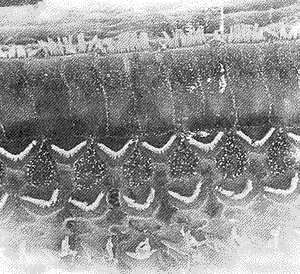

2.3 电镜下观察 正常豚鼠5只、10耳,耳蜗Corti′s器毛细胞结构正常,清楚显示3排呈“V”型排列的外毛细胞及单排内毛细胞,见图2。6只、8耳COM豚鼠耳蜗Corti′s器第3排外毛细胞静纤毛散在倒伏、扭曲、指向不一、融合、顶端粘连、部分 Corti′s器第3排外毛细胞静纤毛片状倒伏,有的失去正常“V”型结构,见图3,4。

图4 电镜下示第3排外毛细胞静纤毛大片倒伏、扭曲、指向不一,顶端粘连,有的失去正常“V”型结构